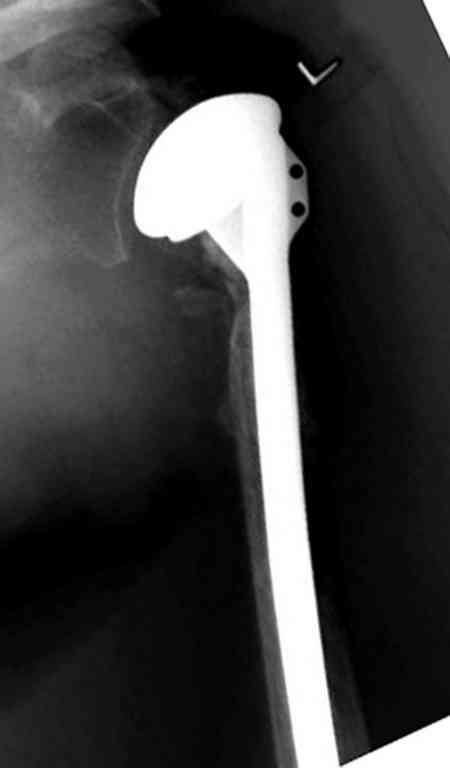

Закрытые репозиции без фиксации из-за вторичного смещения неэффективны, поэтому рекомендуется репозиция с фиксацией. Методик много, кто чем владеет и отдает предпочтение закрытые-открытые, перкутанные, с блокирующими пластинами, гвоздь, множественными спицами или методом спиц по Лазареву, и осторожно с манипуляциями из=за возможности повреждения аксиллярного нерва - частый вид осложнении.

Неправильно выбранная тактика по фиксации или технические ошибки во время операции могут привести к серьезным осложнениям. Здесь привожу

пример из нашей практики, вроде обычный перелом шейки, фиксированный популярным методом "Сиэтла" - множественными спицами 2.8 мм с резьбой на конце.